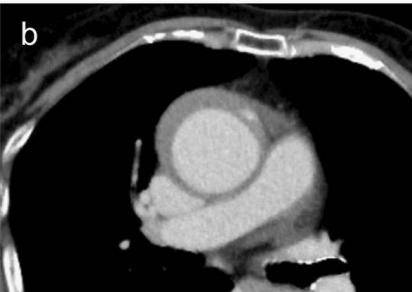

病例4

下图的胸部CT平扫,基本上大约肯定可以看到一条线样阴影,将主动脉一分为二!

图10

增强CT一看,主动脉裂开了!

图11